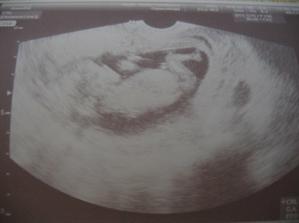

Naše maličké